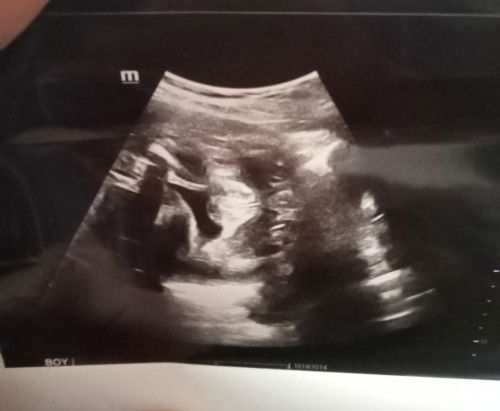

Baby apa ni

hai mumy smua .. mumy tngok ni mcm baby girl ke baby boy .. doktor kata baby boy . tpi sy x nmpk pistol dia .. keliru sy dia buat yer#ingintahu